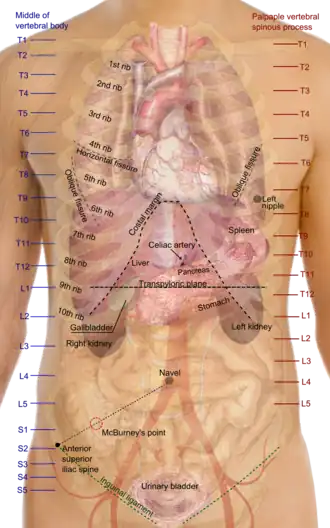

O tórax[1] é uma parte da anatomia dos mamíferos e outros animais tetrápodes localizada entre o pescoço e o abdômen.[2][3] Em insetos, crustáceos e nos extintos trilobitas, o tórax é uma das três principais divisões do corpo da criatura, cada uma das quais, por sua vez, é composta de múltiplos segmentos.

O tórax humano inclui a cavidade torácica e a parede torácica. Ele contém órgãos, incluindo o coração, os pulmões e o timo, bem como músculos e várias outras estruturas internas. Muitas doenças podem afetar o tórax, e um dos sintomas mais comuns é a dor torácica.